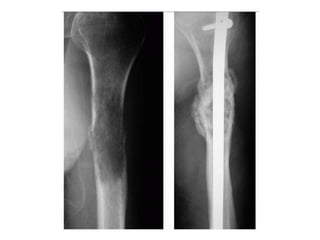

Lobulated partially ill-defined lytic lesion of the proximal Humerus

Plain radiograph showing eccentrically locating ,single Osteoblastic metastasis

Mixed lesion in lung mets